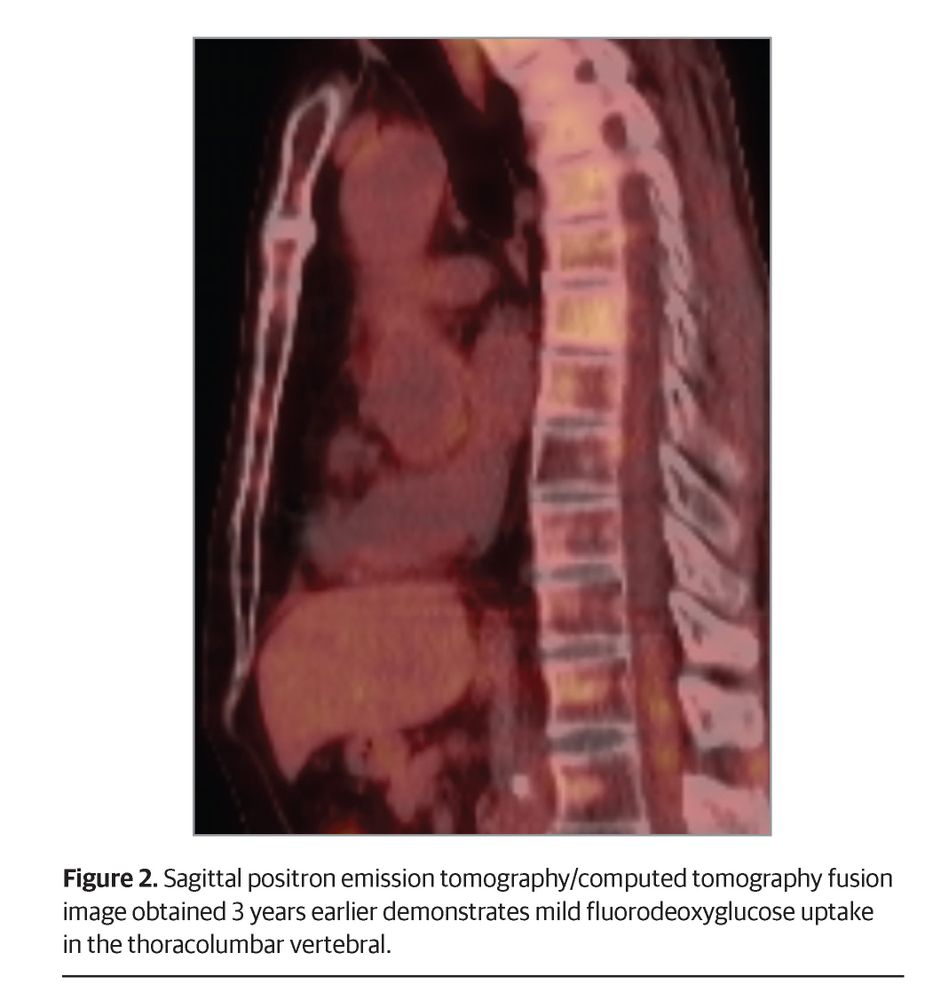

A 62-year-old man with submandibular salivary duct history, alcohol use disorder, and facial flushing after minimal alcohol presents with lower extremity numbness, dysesthesia, and impaired proprioception.

What is your diagnosis? ja.ma/4psymuN